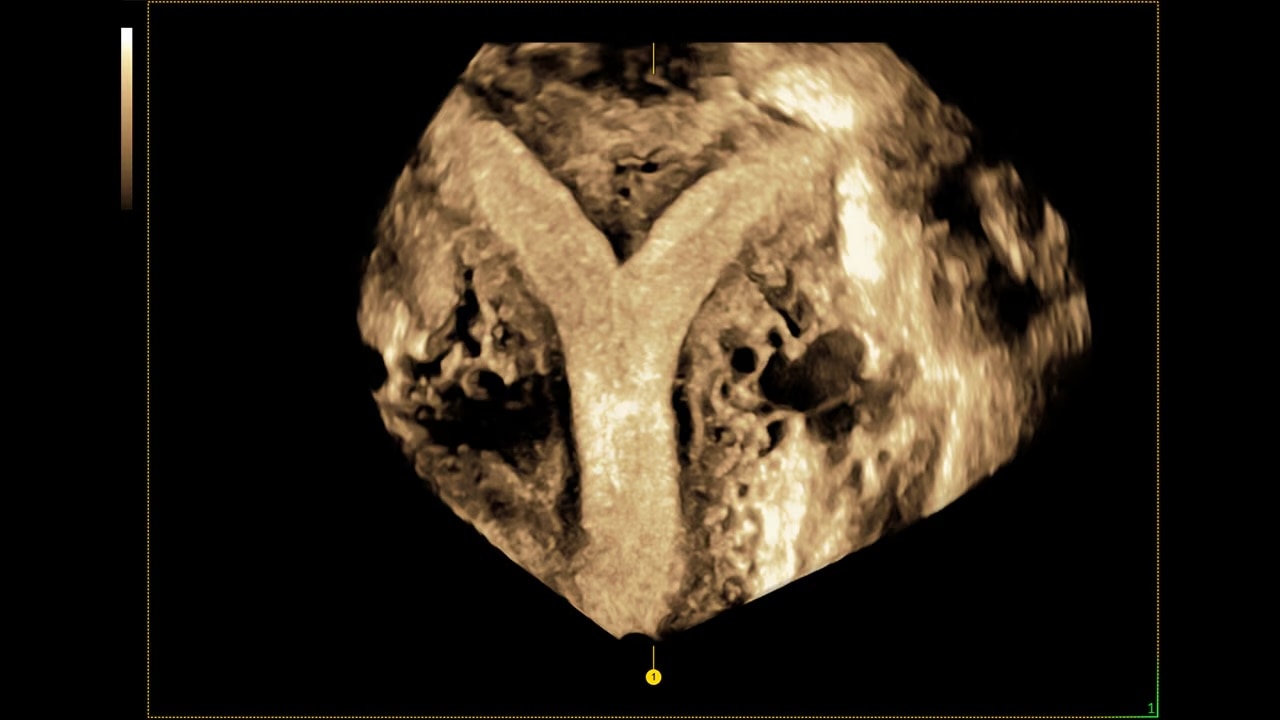

Next level color Doppler that delivers exceptional sensitivity for easy, fast visualization of blood flow, displaying a 3D like appearance as seen in this 27-week fetal heart.